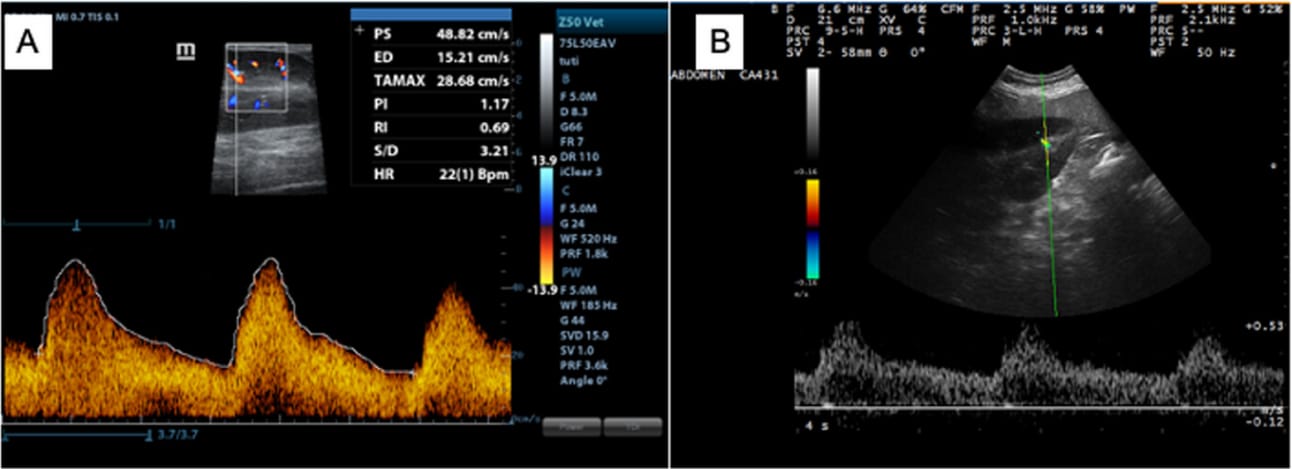

B mode and Doppler images of the left kidney. A, Waveforms acquired through transrectal approach in an adult horse. PS, peak systolic velocity; ED, end-diastolic velocity; TAMAX, average velocity; PI, pulsatility index; RI, resistivity index (Mindray Z50 Vet, linear rectal transducer, 5 MHz). B, Waveforms obtained by the transabdominal approach (eSaote MyLab 30 Vet Gold, convex transducer, 6.6 MHz).

Mean RI and PI values for the left kidney were similar across both techniques (TA RI: 0.545, PI: 0.864; TR RI: 0.554, PI: 0.877). Right kidney values also showed close agreement (TA RI: 0.568, PI: 0.934; TR RI: 0.557, PI: 0.872). No statistically significant differences were found between sides or approaches for either RI or PI. However, acquiring satisfactory TR waveforms for the right kidney was more difficult, particularly in large horses. Overall, image quality for the left kidney was better via TR, while TA was more effective for the right kidney.